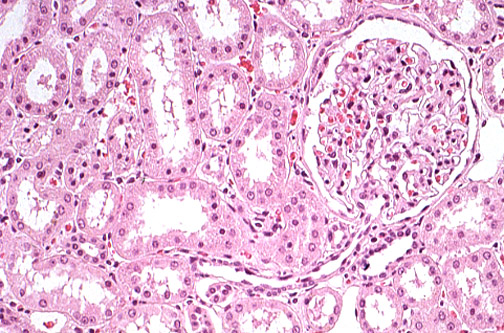

| Yes, the juxtaglomerular apparatus really does exist. Seen here is the afferent arteriole entering the glomerulus at the vascular pole. The juxtaglomerular apparatus is a region of specialized smooth muscle cells called JG cells located in the afferent arteriole which, along with a set of columnar cells called the macula densa in the adjacent segment of distal convoluted tubule, sense changes in blood pressure and sodium concentration. The JG cells secrete renin to maintain blood pressure and volume control. |